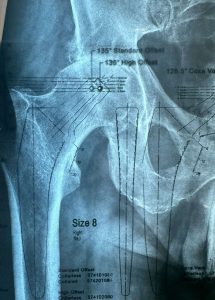

Προεγχειρητικός σχεδιασμός για την ακριβής επιλογή του τύπου και του μεγέθους του εμφυτεύματος.